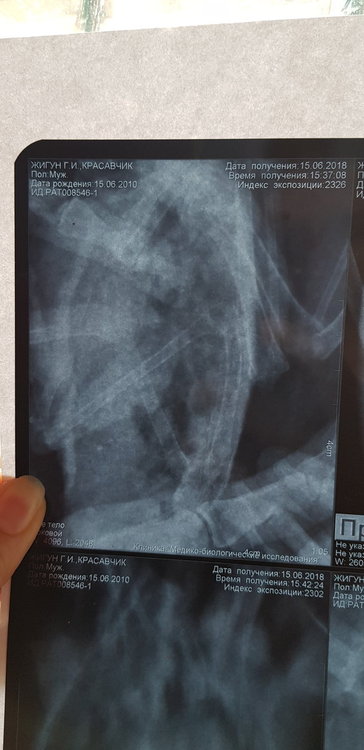

Сделала рентген. Но я в нем не разбираюсь.  Есть ли там грибы в легких. 3 дня по чуть-чуть совсем так чтобы выходило примерно 5 по на день орунгамин. И сейчас ему совсем плохо. Один глаз закрыт, помутнеет. Постоянно пытается отрыгнуть или делает такие движения. Совсем вялый. Фото прикреплю в сообщении ниже